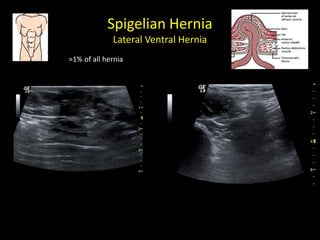

Spigelian Hernia

Lateral Ventral Hernia

≈1% of all hernia

Spigelian Hernia Lateral VentralHernia ≈1% of all hernia